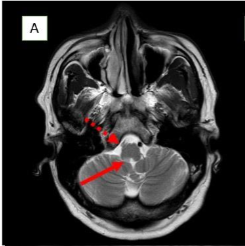

Methods: Two male patients presented with persistent hiccups, nausea, and vomiting. Imaging confirmed lateral medullary infarcts involving the area postrema. Etiological investigations included vascular imaging and thrombophilia workup.

Ischemic Area Postrema Syndrome (APS) is a rare neurological condition characterized by persistent nausea, vomiting, and hiccups resulting from an infarction in the area postrema, a highly vascularized, circumventricular structure in the dorsal medulla. Supplied by small perforating branches of the anterior spinal artery or vertebral artery, this chemoreceptor “vomiting center” lacks a typical blood–brain barrier, making it uniquely vulnerable to ischemic injury. Although ischemic stroke is an infrequent cause of APS, case reports—highlighting dorsal medullary infarcts confirmed on thin-slice diffusion-weighted MRI—demonstrate that small, localized ischemic events can disrupt the area’s function and induce classic APS symptoms.

| MRI Findings | Acute lateral medullary infarct (right area postrema), loss of normal flow void in right vertebral artery and PICA → intraluminal thrombus | Infarct in lateral medullary area, thrombus in right vertebral artery, T2 hyperintensities in bilateral cerebral hemispheres perpendicular to corpus callosum |

Early recognition of APS is crucial for timely diagnosis. In NMOSD, APS can precede MRI findings, warranting early immunotherapy. In contrast to stroke, APS in NMOSD is driven by autoimmune astrocytopathy, where anti-AQP4 IgG binds to astrocytic water channels in the area postrema, triggering complement activation and resulting in astrocyte loss, immunoglobulin/complement deposition, and inflammatory infiltrates. In a stroke, infarction leads to irreversible damage. Ischemic-stroke-induced Area Postrema Syndrome (APS) results from vascular occlusion—typically of perforating branches from the anterior spinal or vertebral arteries—leading to neuronal ischemia, necrosis, and microglial activation within the dorsal medulla, as demonstrated by diffusion-weighted MRI in case reports.